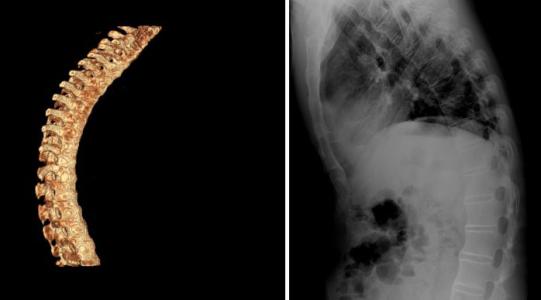

强直性脊柱炎以骶髂关节和脊柱附着点炎症为主要症状的疾病。与HL ...

强直性脊柱炎,是一种原因不明的、以中轴关节慢性炎症为主的全身 ...